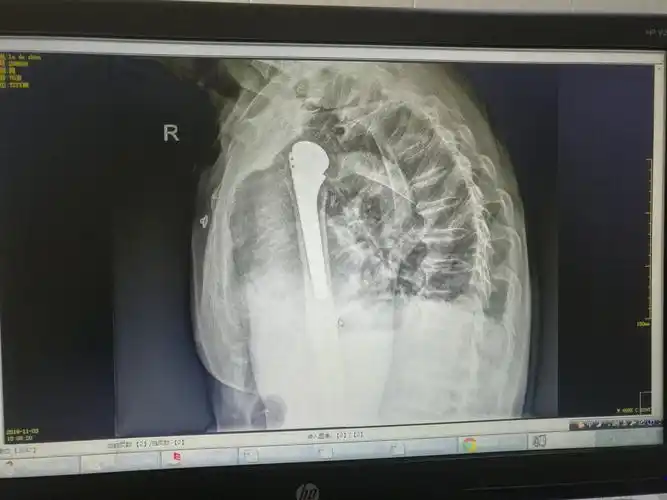

厉害,让老大爷重拾生活信心!德昌县首例人工半肩关节置换术获得成功.

肩关节的摄影体位-素问文库